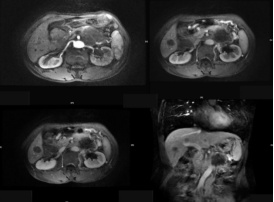

(3)腺囊性肿瘤:浆液性囊腺瘤常发生在胰腺体尾部,老年女性多见。切面呈蜂窝状;黏液性囊腺瘤和囊腺癌,黏液性囊腺瘤常有恶变的可能,实际上潜在的恶性肿瘤。胰体尾部多见,肿瘤常常很大,为单囊或几个大囊组成。

截屏2022-10-06 19.01.50

胰腺黏液性囊腺瘤

截屏2022-10-06 19.02.15

胰腺浆液性囊腺瘤